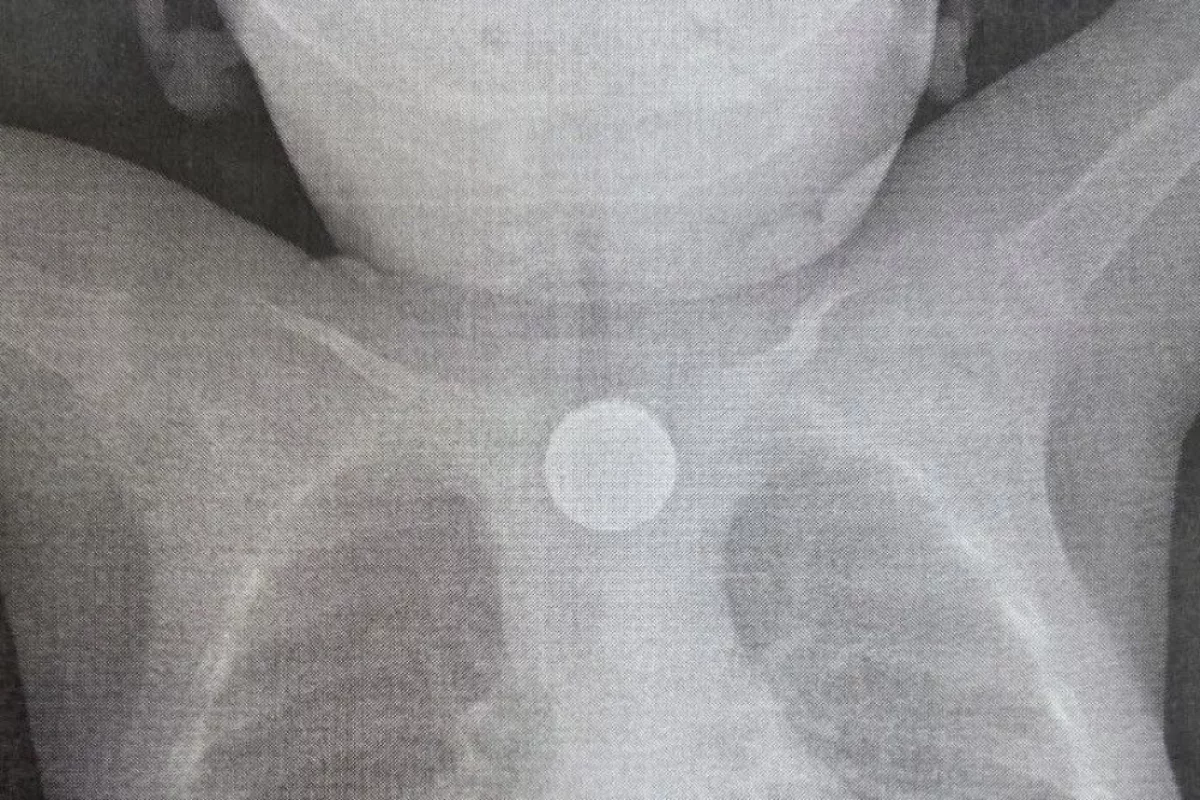

В приёмно-диагностическое отделение больницы доставили годовалого малыша с тревожными симптомами: многократная рвота, повышение температуры, появление хрипов при дыхании. Бригада врачей с помощью эндоскопии вытащила из пищевода ребёнка двухрублёвую монету и дисковую литиевую батарейку.

«Находившаяся в пищеводе батарейка вызвала химический ожог третьей степени, который представлял серьёзную угрозу для жизни ребёнка, — рассказали в медучреждении. — В настоящее время состояние маленького пациента стабилизировалось. Он находится в отделении анестезиологии и реанимации под круглосуточным наблюдением. После дальнейшей стабилизации его переведут в профильное отделение».

«Вопреки распространённому заблуждению, не стоит пытаться вызвать рвоту у ребёнка — если инородное тело застрянет в пищеводе, это может привести к весьма опасным последствиям, — отмечает детский хирург ДРКБ Елизавета Балганжапова. — Также не стоит давать ребёнку еду и питьё. Желательно сразу обратиться к врачу — если вы живёте в Улан-Удэ, нужно ехать в экстренное приёмное отделение, которое работает круглосуточно. Здесь врач-хирург осмотрит ребёнка, и ему сделают рентген грудной клетки, что поможет выявить инородное тело. Если же вы живёте в райцентре или посёлке, нужно обратиться в центральную районную больницу».